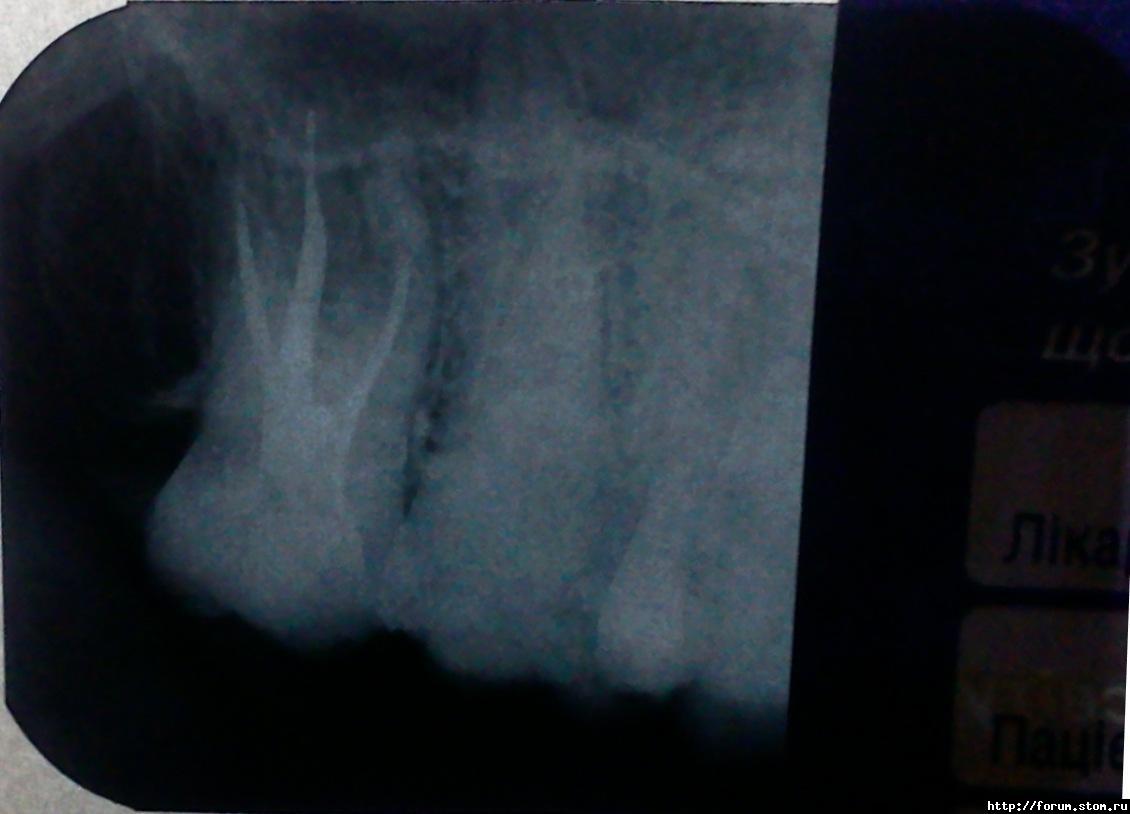

Klima Опубликовано 4 ноября, 2011 Поделиться Опубликовано 4 ноября, 2011 Здравствуйте, хоть и здесь уже на этот вопрос устали отвечать я его задам так как хочу быть уверен всё ли верно говорит мой лечащий врач, или стоит обратится куда-то ещё.В общем ситуация такая 1.11.11 утром почувствовал что вроде как воспалилась десна испугался что это зуб который протезировали так как там было разрежение под зубом 5 но мы его пролечили перед протезированием. зеркалом осмотрел дырка в зубе мудрости.записался на этот же день к врачу на приём анестезия, удаление нерва из канала. Оставили какое-то лекарство на 2 дня . 2 дня зуб болит при надавливании не могу сомкнуть челюсть, на ночь боль усиливается. Пью ношну, имет если сильно разыграется. На 3 день запломбировали канал рентген и временная пломба боль не проходит.назначили физиотерапию электрофорез KJ сказали ускорит процесс заживления и боль быстрее уйдёт.прикрепляю свой снимок может врач чего не досмотрел хочу знать мнение других специалистов (может стоит вообще удалить и не мучать ) забыл когда ем если сошлись челюсти болит как будто мимолётом свет в глазах отключили. Ссылка на комментарий

ger_berra Опубликовано 5 ноября, 2011 Поделиться Опубликовано 5 ноября, 2011 В каналах недопломбировка,поэтому и болит.Исправить это можно лишь грамотно и качественно перелечив каналы.А вообще рекомендуют 8-ки в плановом порядке удалять,т.к. эти зубы очень часто занимают неправильное положение в челюсти,травмируя тем самым слизистую оболочку, не участвуют в жевании,на них быстро образуется кариес(т.к. затруднён доступ к ним для зубной щётки).Лечение таких зубов сопряжено с трудностями из-за неудобства и затруднённого доступа.Удаляйте и не мучайтесь. Ссылка на комментарий

Bier Опубликовано 5 ноября, 2011 Поделиться Опубликовано 5 ноября, 2011 по снимку это больше на 7ку похоже? Ссылка на комментарий

Большой Зеленый Опубликовано 6 ноября, 2011 Поделиться Опубликовано 6 ноября, 2011 по снимку это больше на 7ку похоже?+1Почему?Вы много удаляете верхних восьмерок? Ссылка на комментарий

Большой Зеленый Опубликовано 7 ноября, 2011 Поделиться Опубликовано 7 ноября, 2011 Ну в 90% все таки у восьмерок корни вместе. Ссылка на комментарий